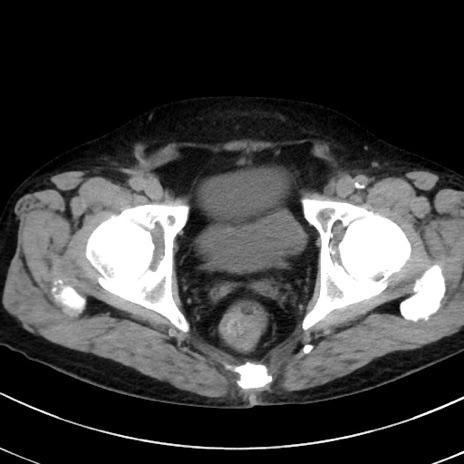

症例38(横断像)

【症例】70歳代 男性

【主訴】腹痛・嘔吐

【現病歴】昨晩より、嘔吐・腹痛あり。今朝になっても嘔吐あり。来院。

【既往歴】心臓バイパス手術、開腹胆摘、腸閉塞

【身体所見】BP 107/71mmHg、HR 116/min、腹部:平坦、軟、下腹部に軽度圧痛あり。反跳痛なし。

【データ】WBC 15100、CRP 0.32